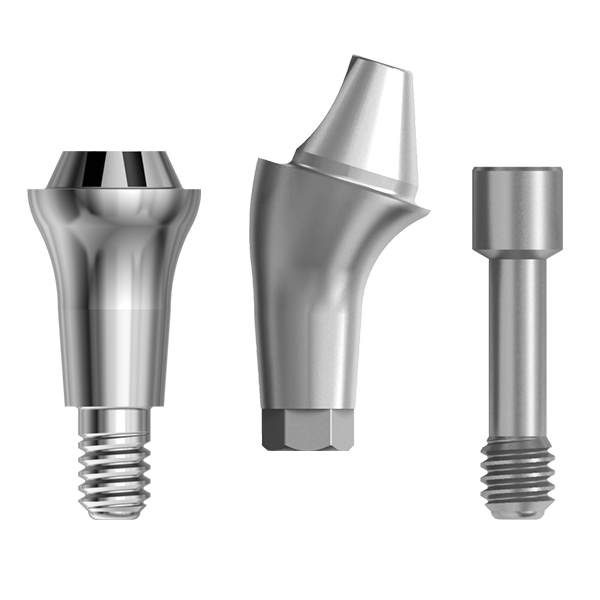

Avec le système In-Kone®, cette technique chirurgicale est associée à l’utilisation de composants prothétiques « tulipés » qui ont vocation à réduire la porte d’entrée aux bactéries potentiellement indésirables et à épaissir les cloisons de muqueuses péri-implantaires(2).